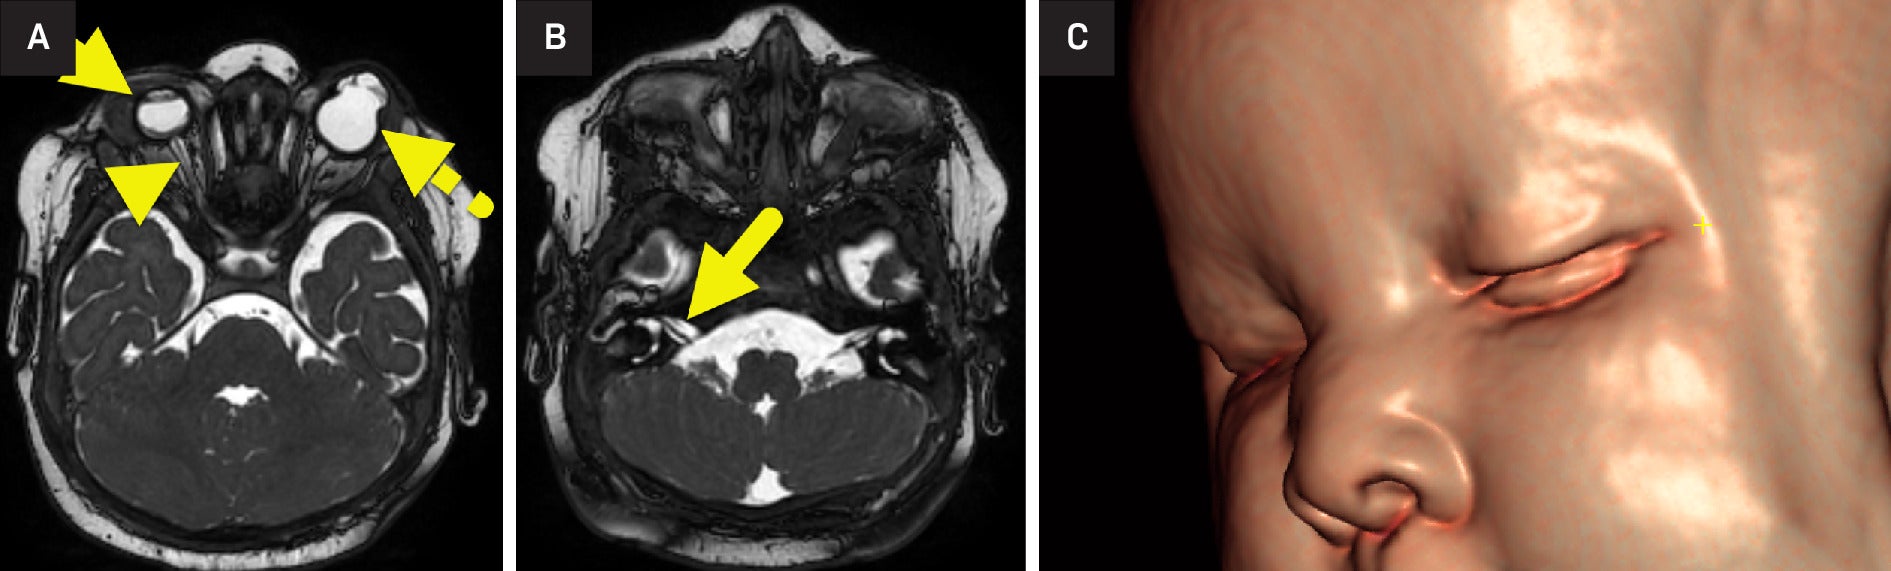

MRI of the brain and orbits ( Figure 1 ) and abdomen ( Figure 2 ) was performed. The right globe was small with a small anterior chamber and a lack of the normal lens. The retina was detached with a small vitreous hemorrhage. The right optic nerve was extremely small and asymmetric compared with the left. The left globe had a bilobed appearance with a cystic area extending into the region of the anterior chamber from the rudimentary orbit. A normal lens was not seen. The cochlear nerves were small, and the cochleae were incompletely partitioned.

(A) MRI of the orbits shows right microphthalmia (arrow). The anterior chamber of the right globe is small, and the lens is absent. The right retina is detached, and the right optic nerve (arrowhead) is small. The left globe (dashed arrow) had a bilobed appearance with a cystic area extending in the region of the anterior chamber from the rudimentary orbit. (B) Images through the internal auditory canal show small cochlear nerves (arrow). (C) 3D reconstruction of the face shows a depressed nasal bridge.